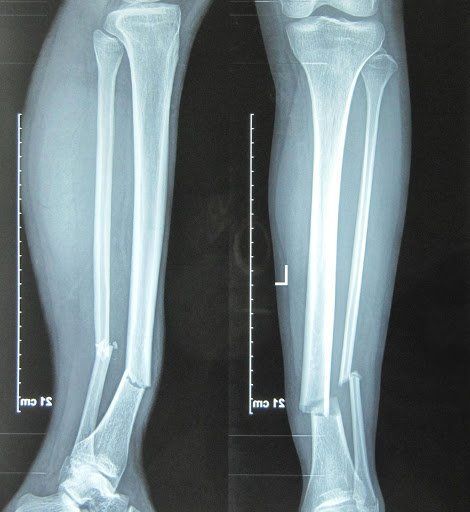

- Gãy xương do stress: thường gặp ở xương chày, xương bàn chân

Hình ảnh XQuang gãy xương chày và xương mác